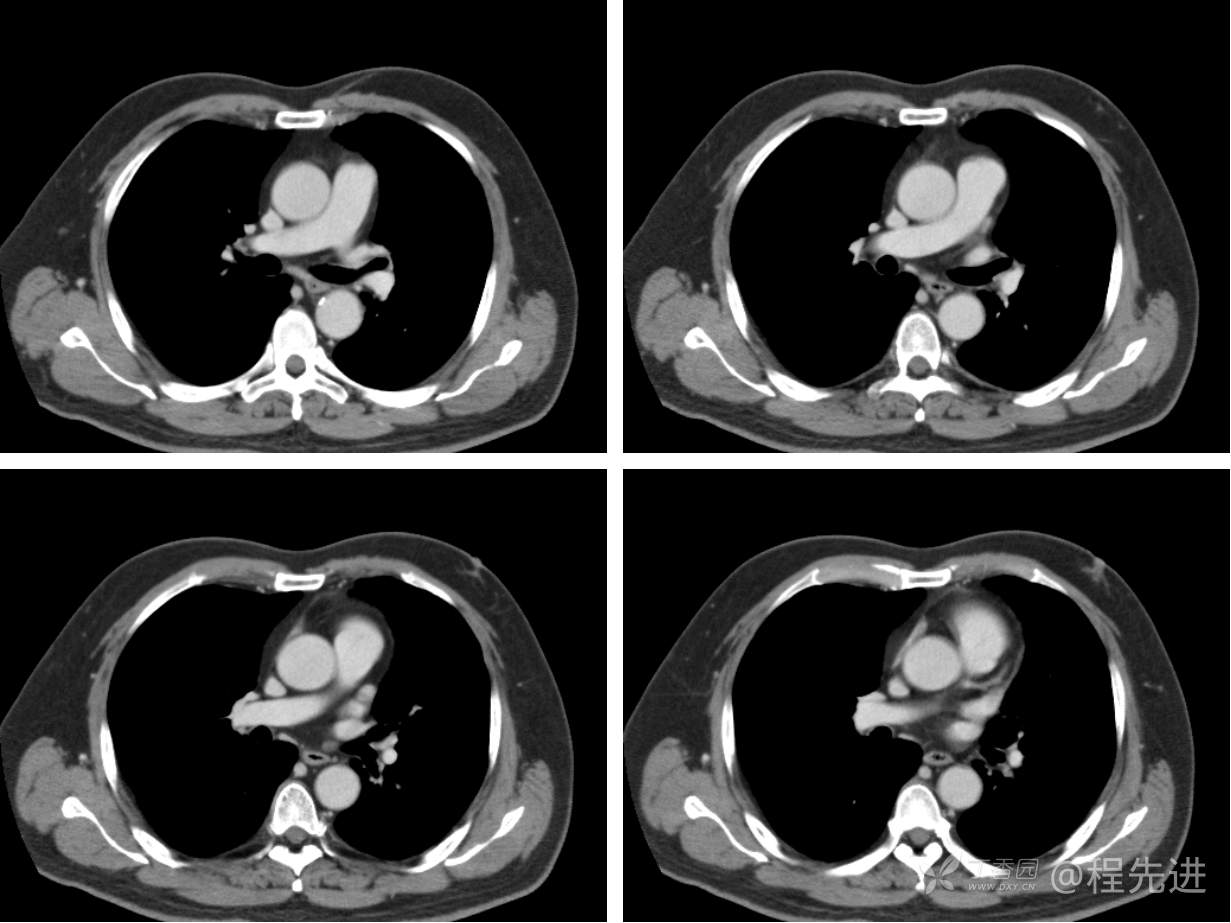

现病史概要:患者入院前约半月无明显诱因下出现咳嗽、胸闷症状,无明显发热症状,咳少量白痰,无明显咯血、喘息、头晕等不适,就诊我院查胸部CT示上纵膈肿物,左肺上叶支气管内肿物,现为行进一步治疗收入胸外科,患者近来饮食睡眠尚可,二便如常。